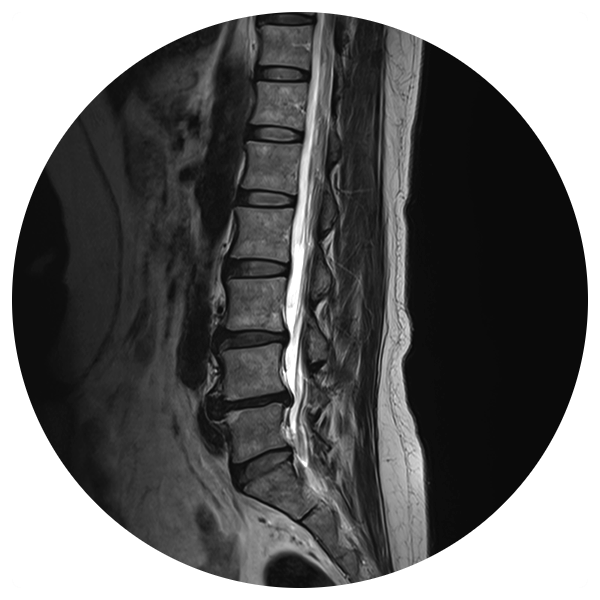

![]()